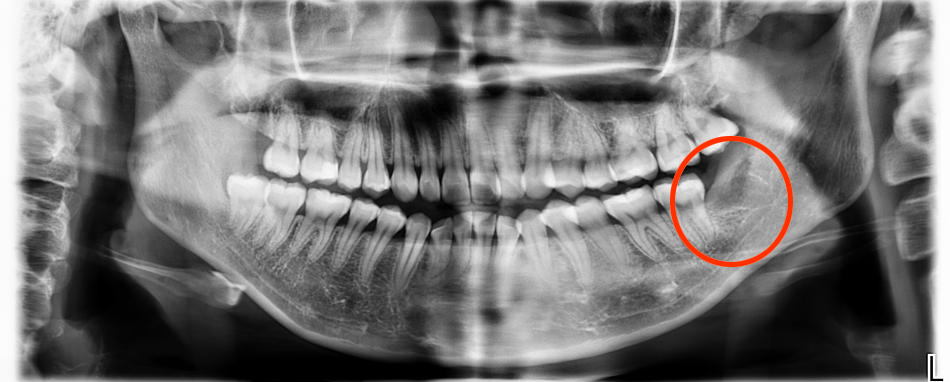

检查显示,崔小姐左侧下颌智齿阻生,紧贴下牙槽神经管

然而,检查结果显示,崔小姐左下智齿深藏于骨组织,牙根部紧贴下牙槽神经管。曾经拔过牙的小伙伴肯定认为她即将留下一段痛苦回忆,并已经开始为她祈祷。

完善相关检查后,崔小姐接受了拔牙。此次拔牙中,陈灵特别使用了科室最新引进的设备——超声骨刀。该设备可释放只对特定硬度骨组织具有破坏作用的高频超声波,精准将牙齿与骨组织分离,不会影响、破坏牙周血管和神经组织,使患者在近乎无痛的状态下接受拔牙治疗。